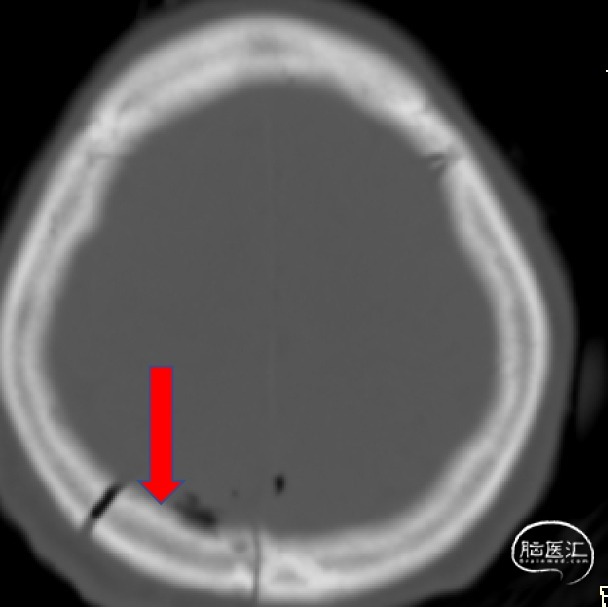

外院影像考虑脑膜瘤?室管膜瘤?

诊断:1.颅内占位性病变(左侧侧脑室三角区,脑膜瘤)2.高血压

术前情况

2023.04.21外院MR

1.结合病史体征及辅助检查诊断左侧侧脑室三角区脑膜瘤明确;

2.肿瘤具有明显的占位效应,无明显的手术禁忌,故手术切除指征明确;